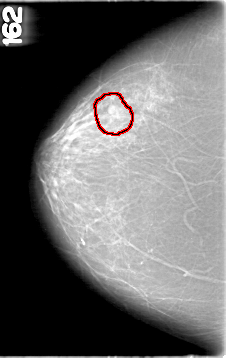

D_4094_1.RIGHT_CC

RIGHT_CC LINES 5356 PIXELS_PER_LINE 3376 BITS_PER_PIXEL 12 RESOLUTION 43.5 OVERLAY

FILE: D_4094_1.RIGHT_CC.OVERLAY

TOTAL_ABNORMALITIES 1

ABNORMALITY 1

LESION_TYPE MASS SHAPE ROUND MARGINS OBSCURED

ASSESSMENT 0

SUBTLETY 4

PATHOLOGY BENIGN

TOTAL_OUTLINES 1

BOUNDARY